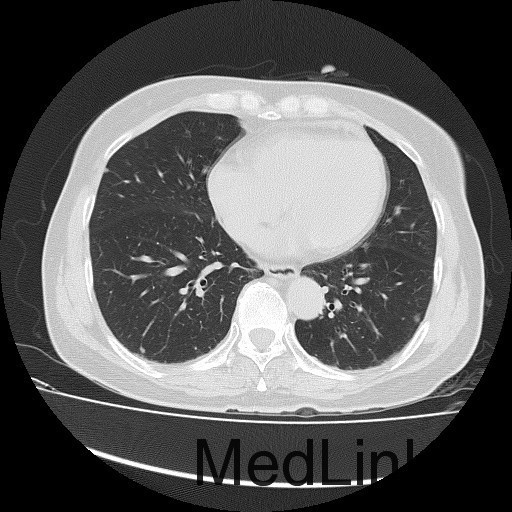

诊断:甲状腺恶性肿瘤(术后);手术后甲状腺功能减退。 治疗:入院时甲状腺球蛋白>455pmol/L,甲状腺素2.793uIU/ml,根据病情于2014-6-3予大剂量碘-131 100mCi清甲治疗;2014年6月全身碘扫示:全身多发异常摄碘组织,考虑甲状腺癌术后双侧甲状腺组织及锥状叶残留并全身多发骨转移。2014年9月胸部CT示:1、双肺多发转移瘤,并胸骨转移;胸1、8、10、腰1椎体内多发结节灶,考虑转移瘤可能性大。2、右肺中叶内侧段、双肺下叶散在慢性炎症。2014年12月全身碘扫:1.全身多处异常摄碘组织,考虑多发骨转移瘤。又于2014年12月复查甲状腺球蛋白抗体90.400U/mL,促甲状腺素6.914uIU/ml。遂于2014-12-22口服250mCi大剂量放射性碘-131。治疗后全身碘扫复查结果提示:2.左肺下叶摄碘组织,不排除转移瘤,建议进一步检查。与2014.6.6检查相比,颈部甲状腺部位放射性浓集灶消失,余病灶放射性浓集程度较前稍降低。

患者又于2015年10月胸部CT复查,结果提示:1、甲癌术后改变;双肺多发转移瘤,大部分病灶较前缩小,左肺下叶病灶较前增多,部分较前增大;胸骨转移;胸1、8、10、腰1椎体内多发结节灶,基本同前,考虑转移瘤可能性大。2、右肺中叶内侧段、左肺上叶舌段及双肺下叶散在慢性炎症。